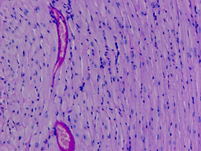

對小鼠心肌組織進(jìn)行PAS染色,來顯示糖原和其他多糖或顯示中性黏液性物質(zhì)和某些酸性物質(zhì),以及軟骨、垂體、霉菌、真菌、色素、淀粉樣物質(zhì)、基底膜等。

組織:小鼠心肌組織

分組:S14、D4

S14

D4

圖1 小鼠心肌的PAS染色示意圖100X

PAS反應(yīng)陽性物質(zhì) 紅色或紫紅色

細(xì)胞核 藍(lán)色

細(xì)胞質(zhì) 深淺不一的紅色